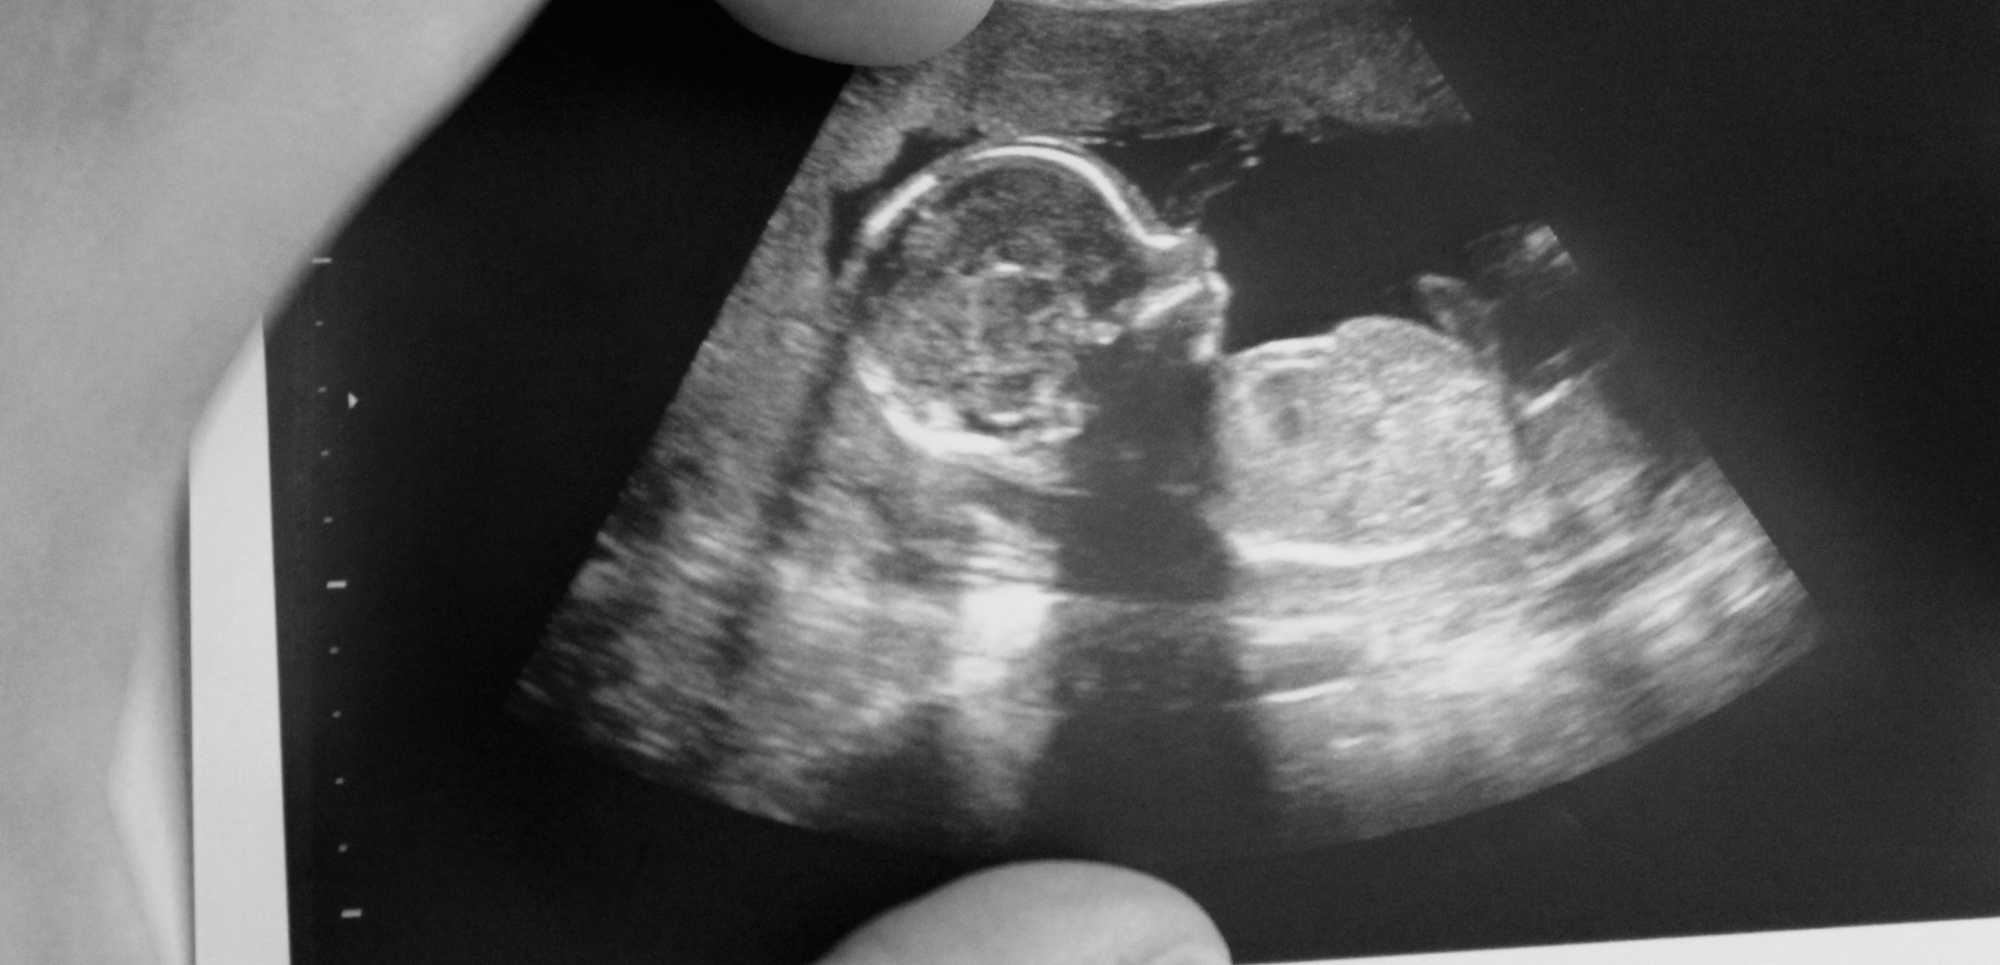

Geralmente, o primeiro ultrassom é realizado entre a 6ª e a 8ª semana de gestação. Nessa fase inicial, o exame já pode detectar o saco gestacional e, muitas vezes, o batimento cardíaco do embrião. Esse exame é fundamental para confirmar a viabilidade da gestação e estimar a idade gestacional, ajudando a definir a data provável do parto.

Durante o primeiro ultrassom, o médico avalia:

- Presença do saco gestacional e embrião;

- Frequência cardíaca fetal;

- Localização do embrião (para descartar gestação ectópica);

- Número de fetos, confirmando se é uma gestação única ou múltipla;

- Estruturas iniciais do útero e ovários da mãe.